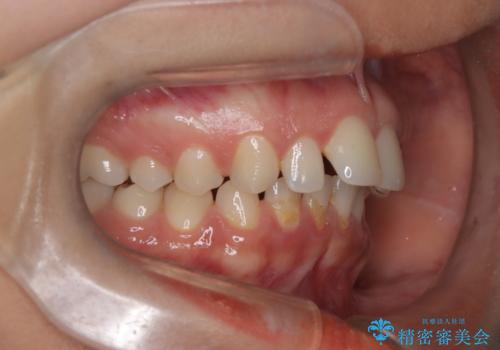

- 患者様は、前歯が出ている状態(上顎前突)と隙間を閉じたいというご希望で来院されました。診断の結果、骨格性の上顎前突が確認されたため、理想的には外科矯正が必要であることを説明しましたが、患者様の「非抜歯でできる範囲で治療を進めたい」という希望を尊重し、矯正治療計画を立てました。治療目標は、前歯の突出を可能な限り改善し、隙間を閉じることに重点を置きました。

本症例では、非抜歯での治療を選択したため、スペースを確保するためにIPR(歯間削合)を行い、歯列を整えました。オーバージェット(上の前歯と下の前歯の水平的なズレ)は残る結果となりましたが、見た目や機能の改善を重視し、患者様と治療計画を共有しながら進めました。治療中は、歯列全体のバランスと噛み合わせを考慮しつつ、矯正装置の適切な使用を徹底しました。当初の計画通りに治療を完了し、患者様にも満足していただけました。